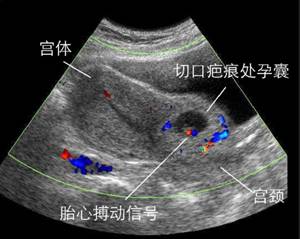

孕囊着床在子宫原疤痕处,常导致阴道大量流血以及晚期的子宫破裂,是较难处理的异常妊娠。这是剖宫产手术后再次妊娠一个严重的并发症,属于宫外孕的一种,非常凶险。如果孕早期出现先兆流产类似的腹痛出血症状,也有可能是疤痕妊娠的早期症状。一般子宫疤痕妊娠通过B超是能发现的,所以针对有过剖宫产史的女性,再次妊娠早孕时必须进行B超检查,早期发现有助于避免子宫破裂和出血,从而便于及时处理。

(图:疤痕妊娠)